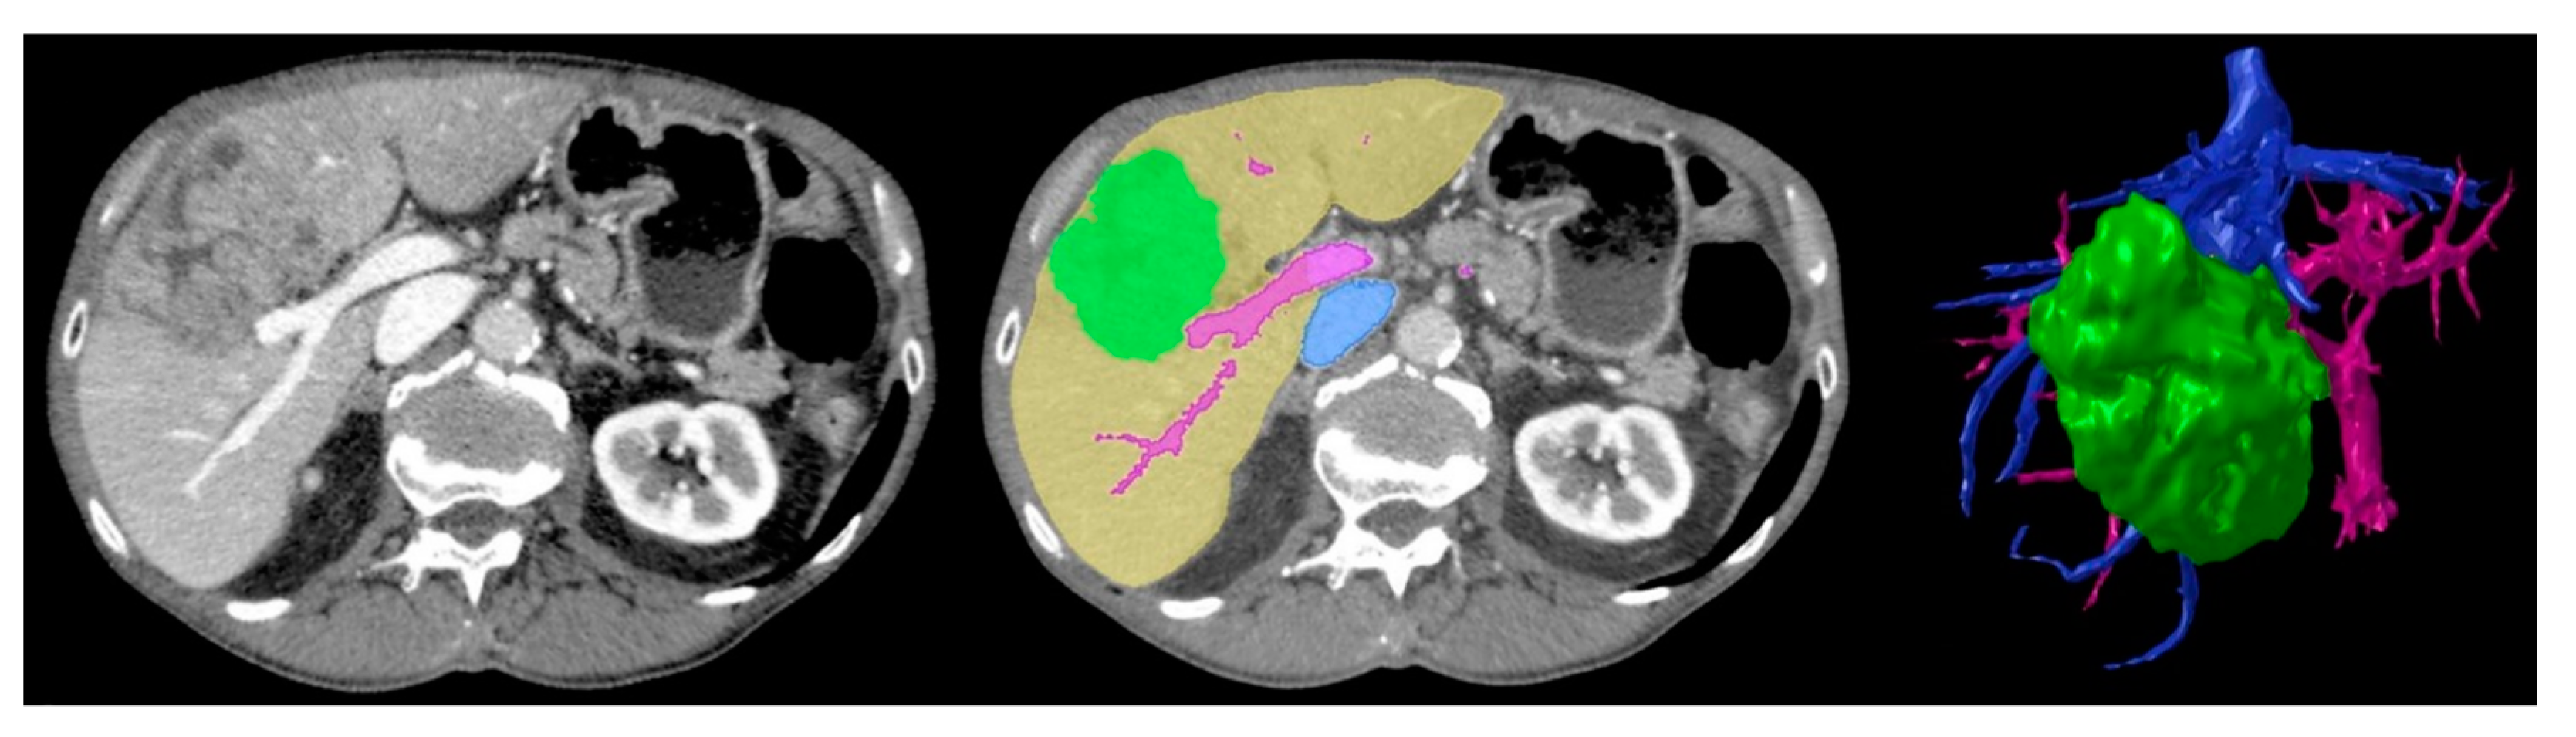

Traditionally, LCR surgical planning is based on a patient’s CT and/or MRI imaging. The surgeon uses 2D axial/multiplanar images and 3DVRs to determine appropriate resection planes and vascular/biliary reconstruction approaches. This requires using images on a 2D screen to construct a 3D mental visualisation of sophisticated patient liver structures. 3DPLMs can facilitate this task by providing a transparent [13,14,15,16,17,22,31], colour-coded [12,15,16,19,22,32,34,35,36,40], tactile [11,14,15,16,40], manipulable [11,14,16,19,29,31,40] and highly cognisable [14,15,16,17,19,29,31] representation of individualised patient liver anatomy, which improves comprehension of the complex and highly variable 3D spatial relationships between intrahepatic structures [14,16,19,22,29,31,33,40] and enhances cognitive localisation of liver tumours [15,16,17,29], as demonstrated in Figure 2. The improved anatomical perception assists surgeons in selecting the most appropriate surgical strategies [11,14,16,17,19,29,33,40], resection planes [13,16,17,33,40], and vascular reconstruction approaches [13,40].

Figure 2.

Three-dimensional spatial location and relationship of liver tumour (T) with intrahepatic anatomy can be better appreciated using 3DPLM (right) compared to CT (left). Reprinted with permission under the open access from Cheng et al. [29].

Segmentation involves digitally extracting the individual voxels within a patient’s imaging volume, which correspond to the liver parenchyma and separate intrahepatic structures and lesions [12,50]. Segmentations are exported in a file format—typically stereolithography (STL)—that uses a tessellated polygon mesh to represent the 3D hepatic structures’ surface geometries [12,14,15,16,22,34,35]. The 3D printer uses these files to produce a 3D-printed model [12]. Figure 5 demonstrates an example of a final STL rendering used for 3DPLM production, compared to a segmented CT image slice and original CT image slice from the corresponding patient imaging data.

Figure 5.

Baseline CT image (left) vs. segmented image (middle) where green = tumour, yellow = liver parenchyma, pink = arterial vasculature, blue = venous vasculature, vs. final STL 3D rendering (right) demonstrating corresponding anatomical structures. Reproduced with permission under the open access from Witowski et al. [17].